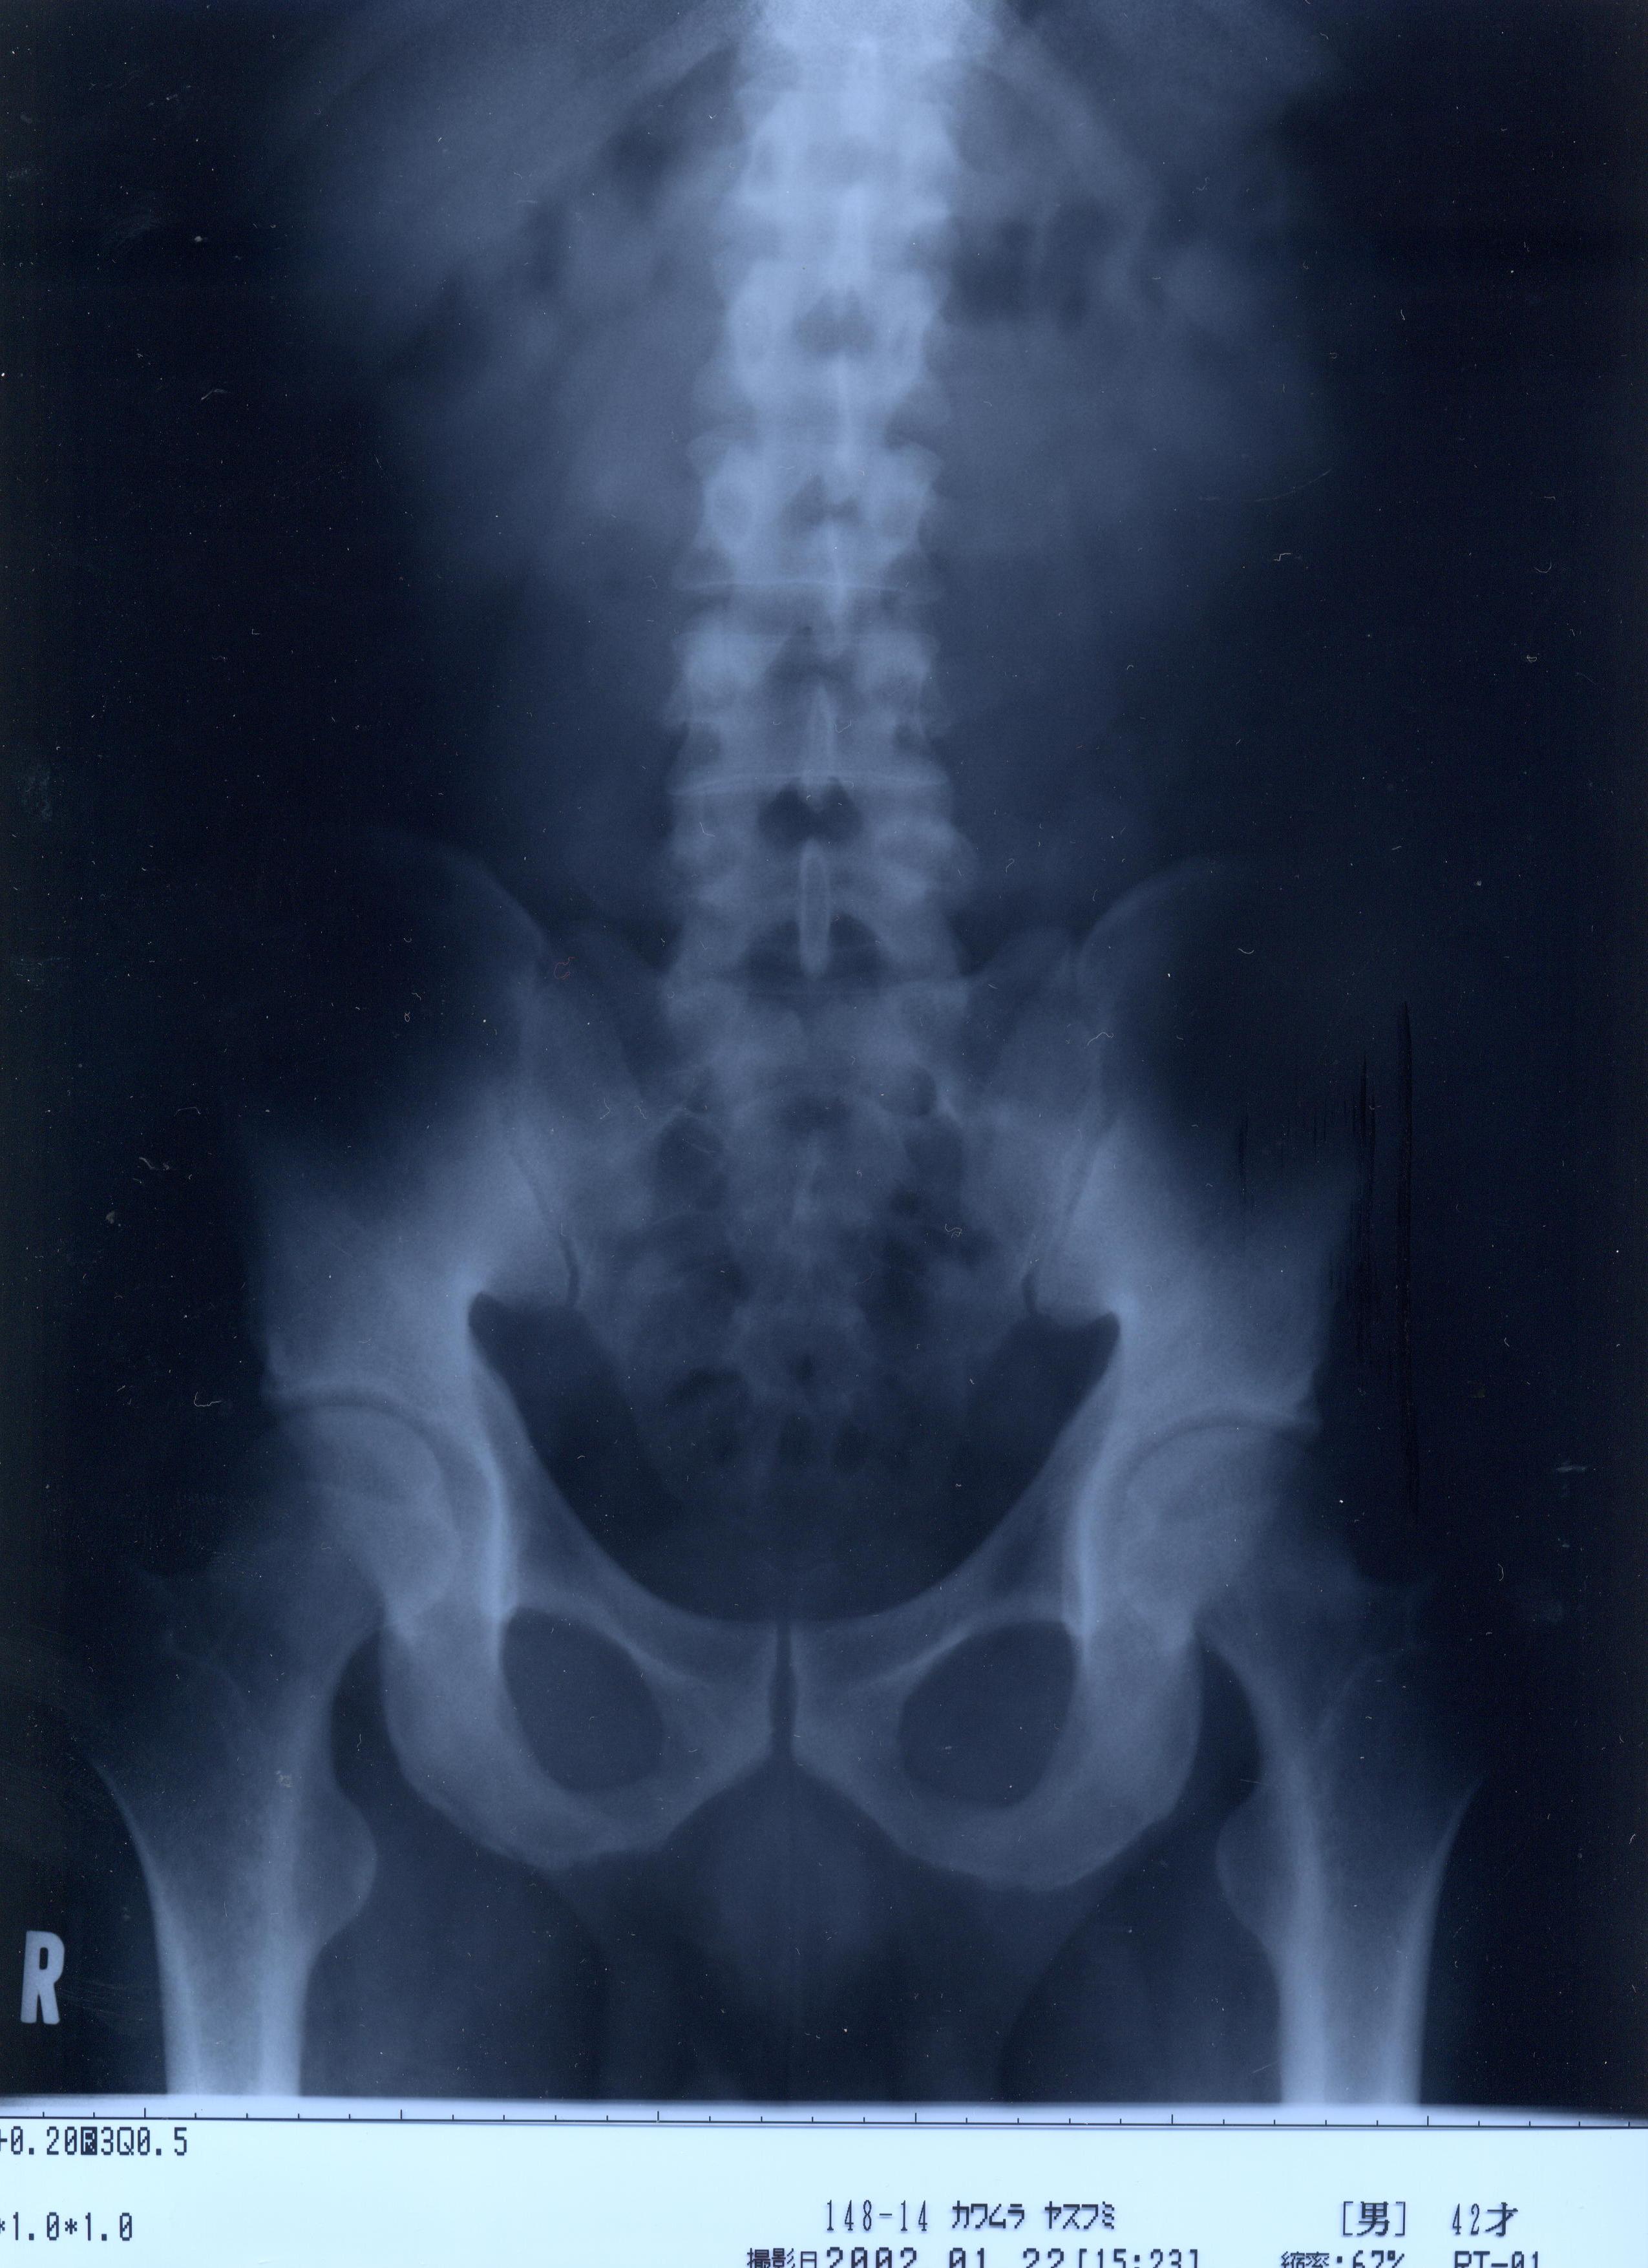

@@Ž„‚Μ”wœ‚Μ‚wόŽΚ^‚Ε‚·@@˜‚ͺ’Ι‚­‚Δ’Ι‚­‚āII@2002/1/22ŽB‰e

‚RDŽρ‚Μ‰‘}@Šg‘ε